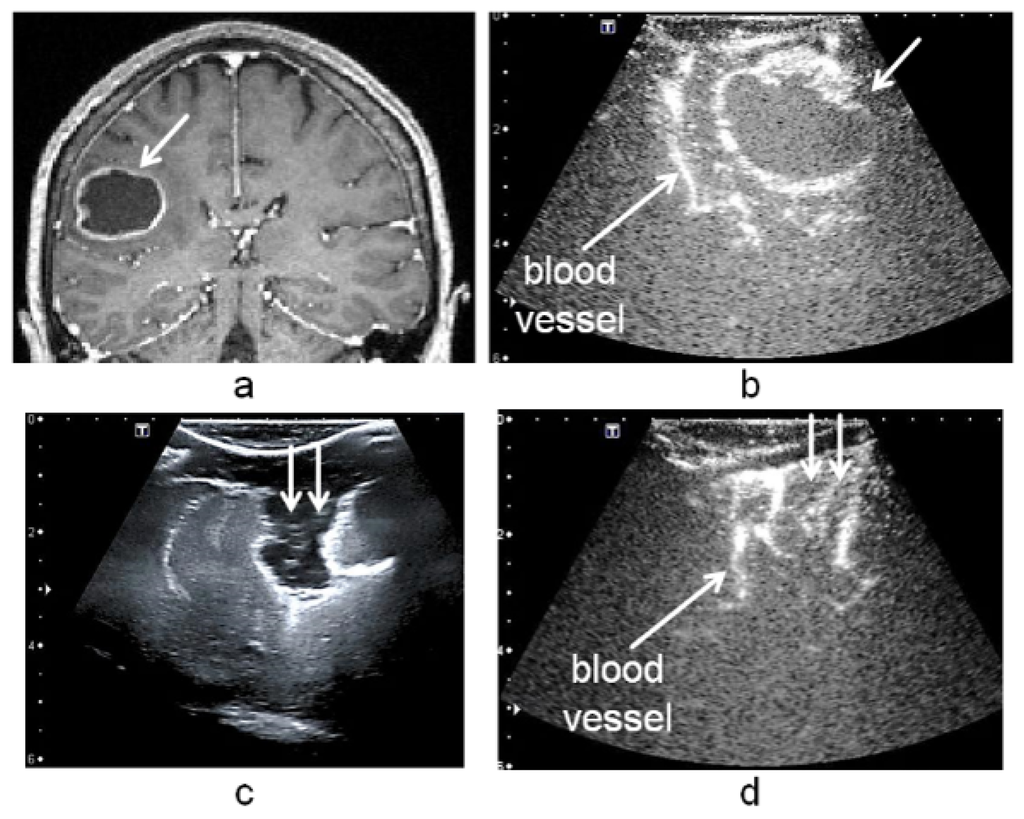

- Step 1: Selecting a vascular segment pattern in cT1MRInteraction with the application in the operating room has to be limited because of sterilization constraints and restricted time. Due to this, during the operation planning, the user delineates interactively a region of interest including a blood vessel near to the tumor in the cT1MR data. The vascular structure is segmented using the method described in Section 2.2. It performs well because the blood vessels are enhanced in the cT1MR data due to the contrast agent, and any other anatomical structure represented with similar intensities is included in the region of interest. The segmented blood vessel represents the pattern (white frame, Step 1, Figure 3) that is searched for in the 3D-iCEUS and 3D-iCEUS data.

- Step 2: Blood vessel identification in 3D-iCEUSThe pattern is firstly searched in the 3D-iCEUS data acquired before resection. In order to reduce the computing time, the search space (large white frame, Step 2, Figure 3) is smaller than the entire 3D-iCEUS, but large enough to take the tissue deformations into account. It has twice the volume of the region of interest defined in the cT1MR data, and is centered on the same image position. The enhanced structures in this region are segmented and then a rigid registration method is used to find the sample in the 3D-iCEUS data (yellow frame, Step 2, Figure 3) which corresponds best to the pattern. A rigid transformation is sufficient here, since the goal is the identification of the position of the blood vessel in the 3D-iCEUS data, which looks like the vascular segment pattern selected in the cT1MR data. The blood vessel detected in the 3D-iCEUS then becomes the new pattern, which has to be identified in the 3D-iCEUS data after resection.